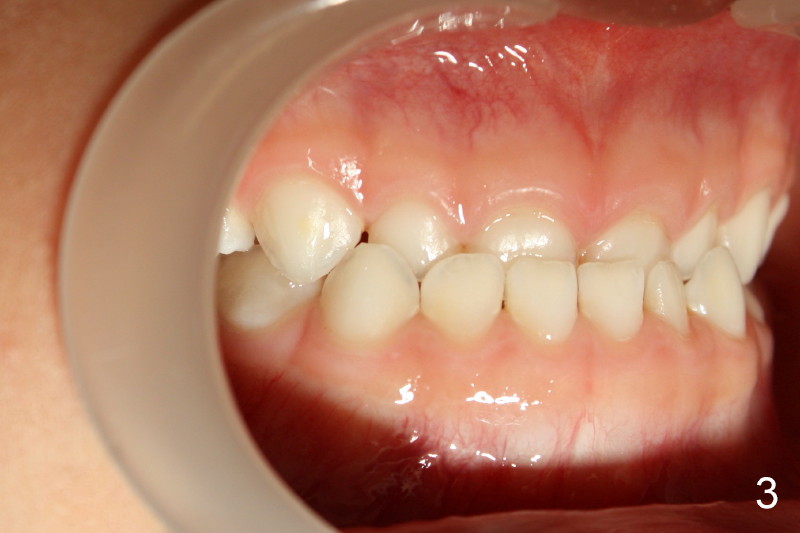

Both sides of molar relationship are in mesial step, left being more severe (Fig.5,6).